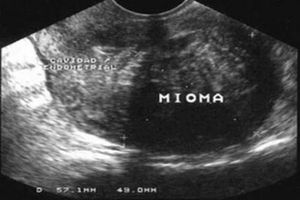

Olá me chamo Ariane Conceição, minha mãe está com vários miomas uterinos. Minha mãe tem 54 anos. Ela está muito fraca por sempre ter hemorragia e os anticoncepcionais já não faz mais efeito nela e não para mais os sangramentos, já tentamos opera-lá no SUS mais não tivemos sucesso. Já coloquei ela no sistema do SUS o SISREG mais também nada. Ela tem esses miomas há mais de 10 anos e semana passada dia 19/03/2023; quase perdi ela com fortes sangramentos que levou a uma hemorragia e anemia moderada. E já tentei também ver particular, mais é muito caro e tentei até juntar dinheiro mais sozinha e desempregada é muito difícil; até que então me recomendaram a fazer a Vaquinha On LINE e aqui estou.

Conseguir um médico que opera miomas e ele cobrou R$ 4.000 reais, sendo que vai ter o pós - operatório com os custos do remédios e etc.... Peço a ajuda de vocês por favor serei eternamente grata por quem ajudou, e queria e não tem condições de ajudar. Que Deus abençoe poderosamente a cada um.

Esse dinheiro vai ser direto pra cirurgia dela, que seria os R$ 4.000 reais. O restante do dinheiro vai ser pra comprar remédios, gases, algodão e etc ... Coisas que irei precisar comprar pro Pós - operatório dela e fora a alimentação dela.